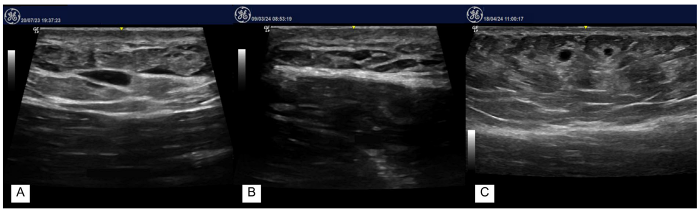

一篇針對臀部交聯型玻尿酸的研究,使用超音波影像追蹤:

(A)術後12個月可見界線清楚之低回音玻尿酸聚集區,周圍未見異常血流。

(B, C)術後20個月追蹤,玻尿酸殘留體積減少,但仍可於皮下層清楚辨識低回音結構,顯示填充物並未完全吸收,且與周邊組織呈穩定整合狀態。案例主觀滿意度高(GAIS 評分為改善或顯著改善)。